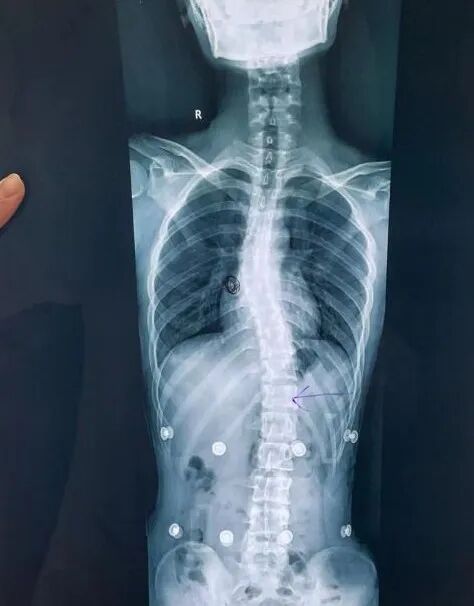

治療前側(cè)彎10度,治療后接近0度